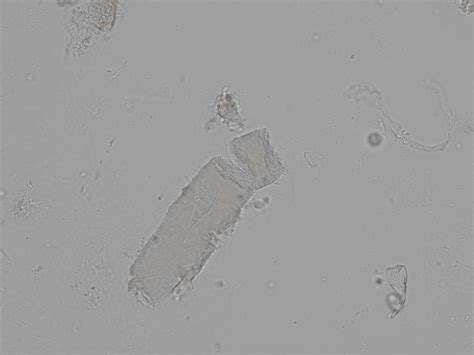

Waxy cast urine, also known as waxy casts, is a medical condition that can indicate various underlying health issues. These casts are cylindrical structures composed of Tamm-Horsfall protein, which are typically found in the urine of individuals with certain kidney disorders. Understanding the causes, symptoms, and treatment options for waxy cast urine is crucial for early detection and effective management of related conditions.

Waxy cast urine refers to the presence of waxy casts in the urine. These casts are formed when Tamm-Horsfall protein, a glycoprotein produced by the kidney's distal tubules, becomes trapped in the urine. The waxy appearance is due to the protein's ability to harden and form a cylindrical shape. Waxy casts are often associated with chronic kidney disease and other renal disorders.

• Urinalysis: A urine test can detect the presence of waxy casts and other abnormalities. The urine sample is examined under a microscope to identify the type and number of casts.